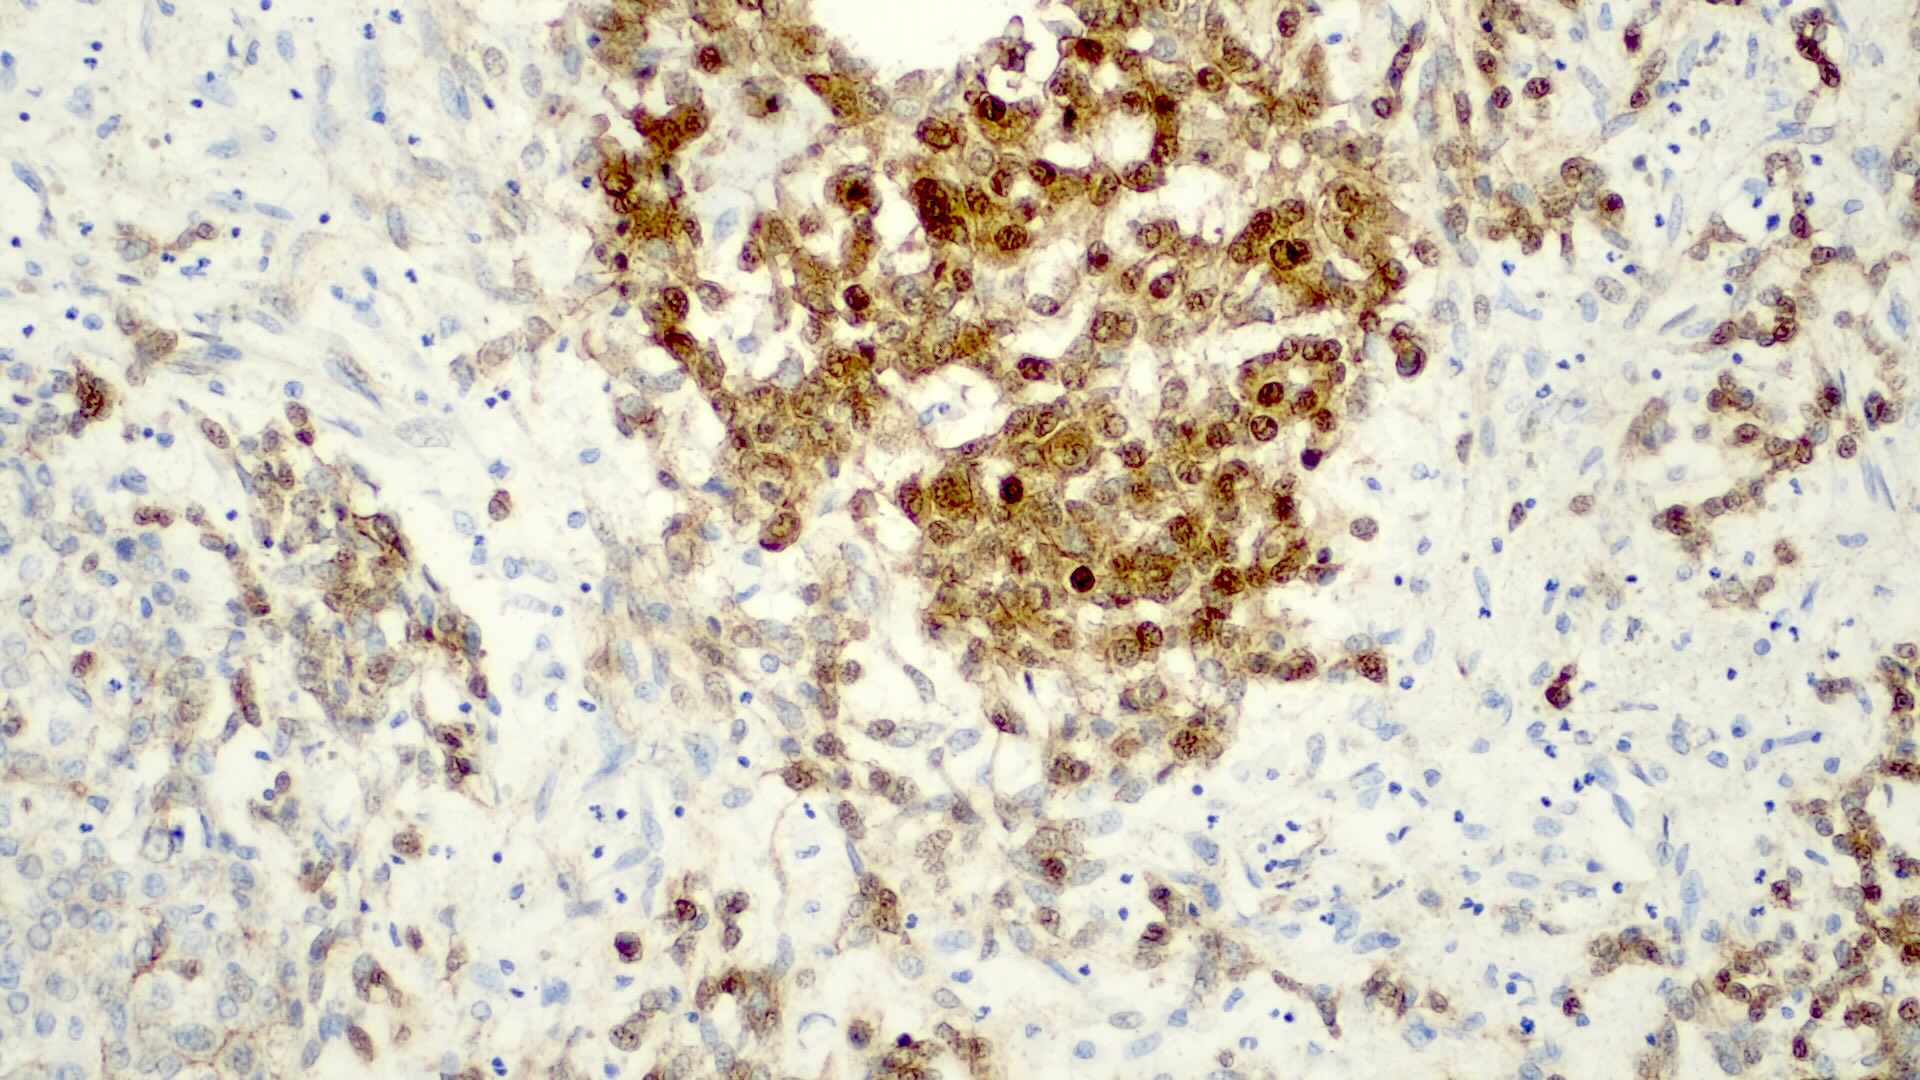

Microscopic (histologic) description

- Classified by the International Pediatric Liver Tumor Consensus Classification as epithelial or mixed epithelial and mesenchymal

- Epithelial hepatoblastoma may exhibit several patterns (alone or in combination): fetal, embryonal, small cell undifferentiated (SCUD), cholangioblastic and macrotrabecular (J Gastrointest Oncol 2018;9:326)

- Fetal pattern (Pediatr Dev Pathol 2020;23:79)

- Thin trabeculae or nests of small to medium sized cells resembling hepatocytes of the developing fetal liver

- Clear or finely granular cytoplasm with variable amount of glycogen and lipids

- Small round nucleus with indistinct nucleolus

- Foci of extramedullary hematopoiesis are usually present

- Typically has low mitotic activity, referred to as well differentiated hepatoblastoma

- A subset has increased mitotic activity, with decreased cytoplasmatic glycogen and pleomorphic nuclei, referred to as mitotically active hepatoblastoma

- Embryonal pattern (Pediatr Dev Pathol 2020;23:79)

- Resembles the developing liver at 6 - 8 weeks of gestation

- Solid nests or glandular / acinar morphology, with papillae and pseudorosettes

- Dark and granular cytoplasm without glycogen or lipids

- Enlarged nuclei with coarse chromatin, resembling blastemal cells

- Extramedullary hematopoiesis is usually absent

- Increased mitotic activity

Microscopic (histologic) images